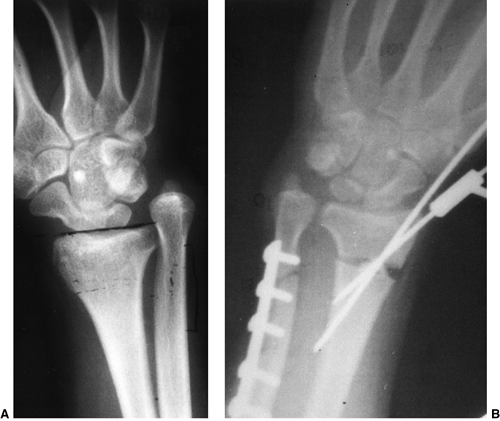

synostosis show anatomic variations from minor radial head deformities

absence of the radial head in patients with no rotation (105) (Fig. 23.8).

Once this position is achieved a second percutaneous Kirschner wire

distal radius, across the derotated synostosis (Fig. 23.8). Because there is a high risk of compartment syndrome postoperatively (139,149),

it is important to avoid internal fixation that would require a second

bone at the synostosis site (136), or dorsal and volar fasciotomies through the operative incision, lessen the risk of compartment syndrome postoperatively (84) and should be performed routinely.

![]() |

Figure 23.8 A:

Preoperative radiograph of a congenital radioulnar synostosis. There is complete fusion of the proximal radius and ulna, and posterior dislocation of the radial head. The entire ulna is mildly hypoplastic. B: Postoperative radiograph of a derotation corrective osteotomy for this patient. A longitudinal wire is passed down the medullary canal of the ulna across the synostosis site. This Kirschner wire starts from the proximal ulnar apophysis. The osteotomy cut is performed through the synostosis. The transfixing wire is obliquely placed to secure the corrective derotation to a position of 0 to 20 degrees of pronation. |